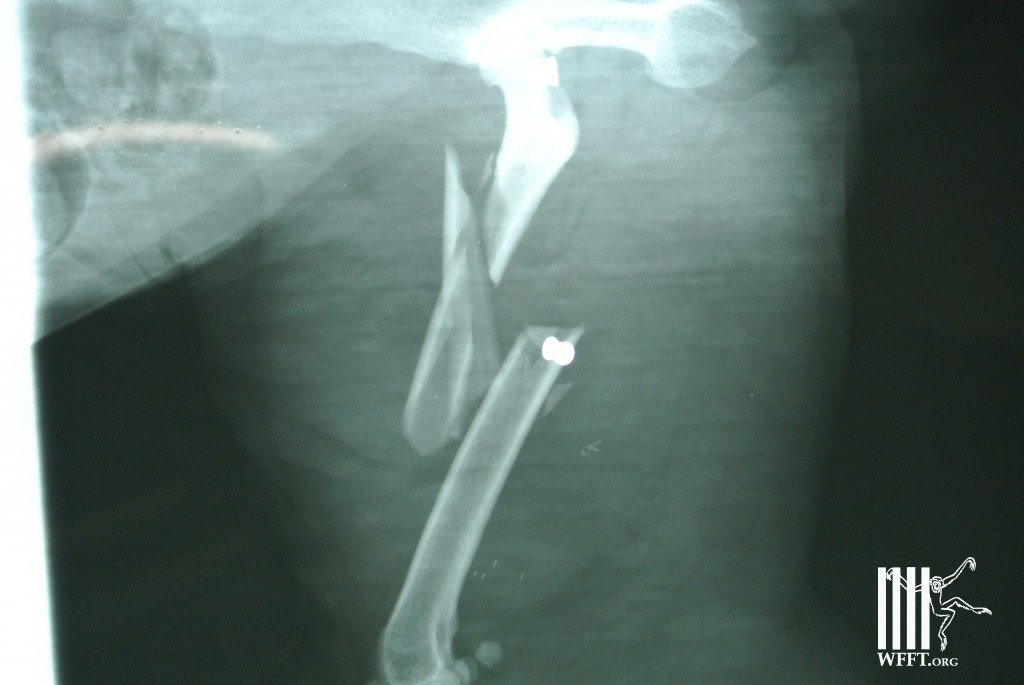

Here under some of the photos of the day of her rescue, she was very illusive and it took us a few hours to catch her as she knew her surroundings better than we did! Once Brenda was caught we found she had a multiple fracture and even had pellets from guns in her body (as seen on x-ray photo). She was taken to WFFT for further treatment and was found completely healed last week.